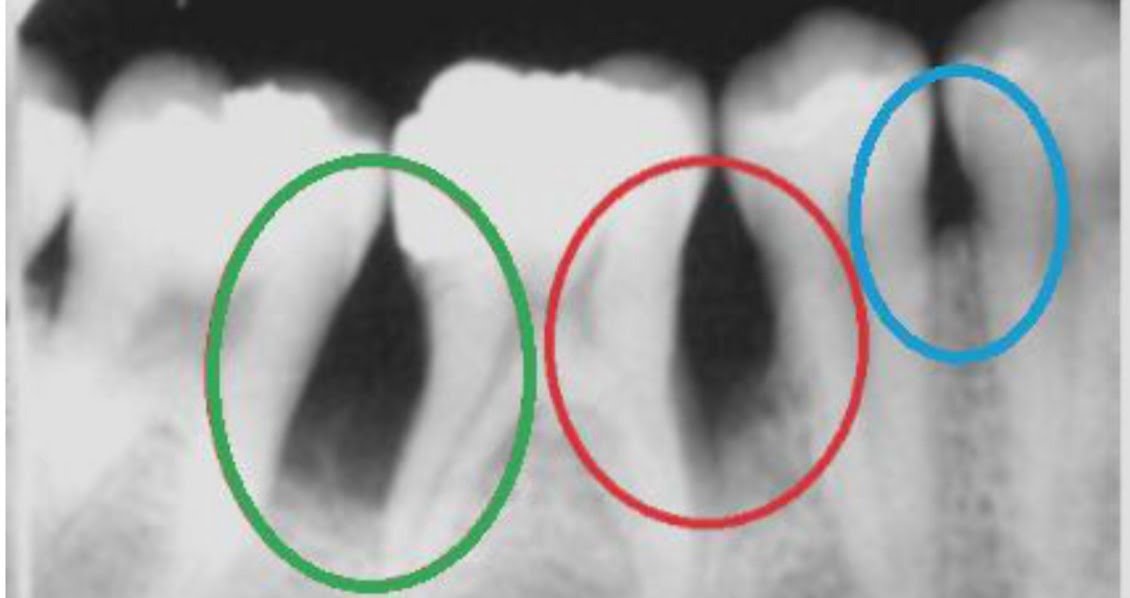

Dental X-rays are a great diagnostic tool for the dentist as they can help us see what cannot be seen through naked eyes which includes the root under your gum as well as your jaw bone.

Dental conditions like cavities, bone loss, cysts, abscesses, fractures, and impaction of teeth can be seen on an x-ray.

RVG is a digital X-ray. It has minimal radiation exposure and the image is produced on the screen within seconds. It gives detailed information with accurate features of specific teeth or the region while being comfortable for the patient.